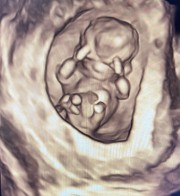

บ้านนี้ไปซาวด์ตอน7สัปดาห์